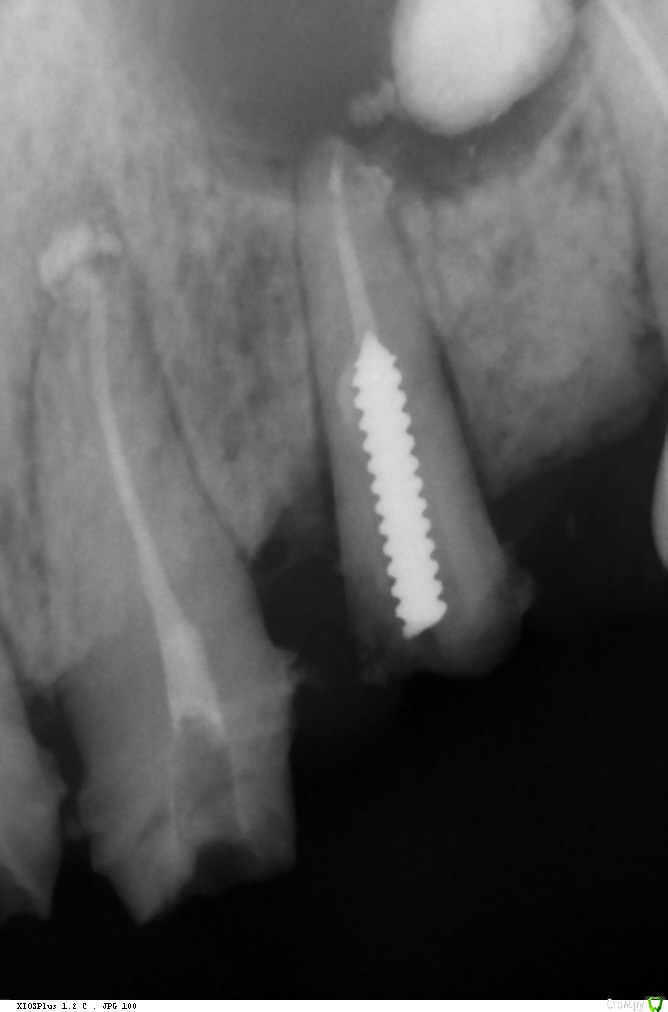

Ponchik Опубликовано 17 ноября, 2015 Поделиться Опубликовано 17 ноября, 2015 (изменено) Пациента ничего не беспокоит. В анамнезе травма 2 сегмента 7 лет назад. Пришел с целью протезирования. Ортопед удалили 22 и направил кисту убрать. Сделали прицельный.Потом захотелось КТ. КТ вышло не очень, но общее представление составить можно. Появились вопросы. На сколько велика вероятность встречи с синусом? Стоит делать амбулаторно? Опыт до этого - цистэктомии в пределах 1-2 зубов. Думаю куда направить. Изменено 17 ноября, 2015 пользователем Ponchik Ссылка на комментарий